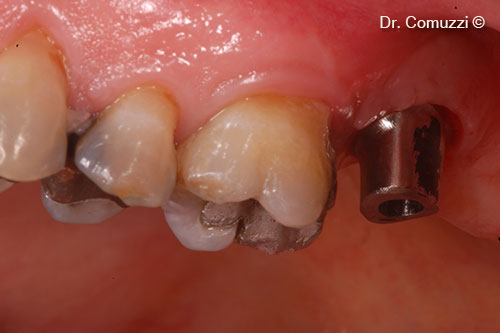

8. Impression coping